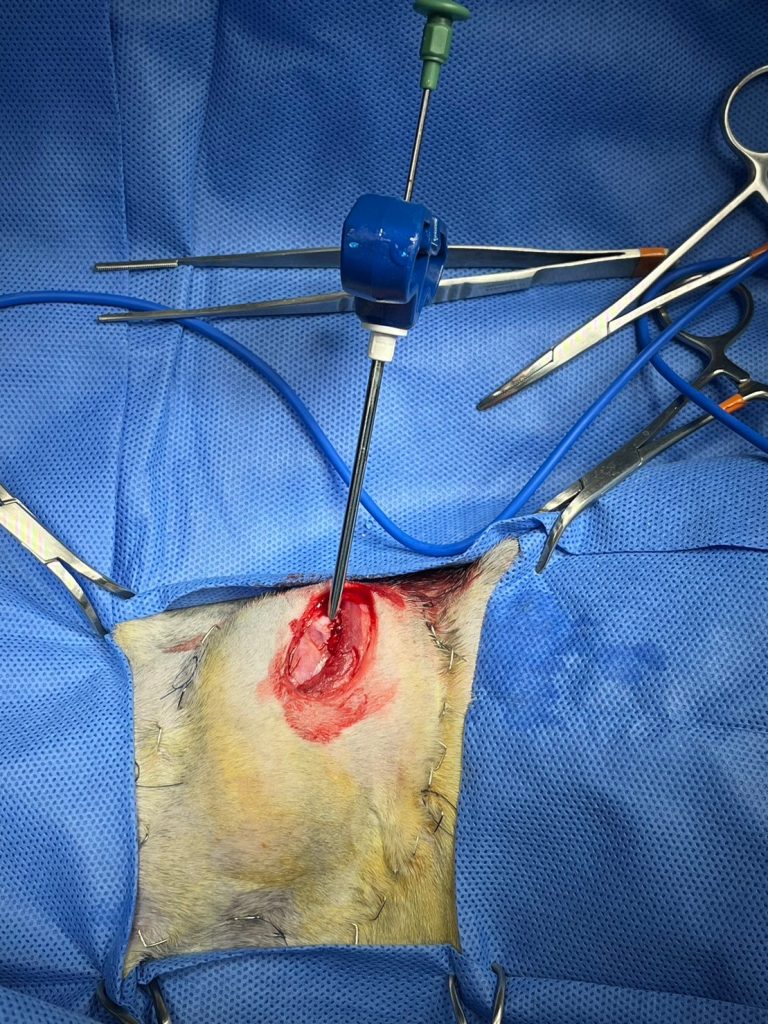

我們選定了一天將毛孩麻醉,劃開團塊上方的皮膚與肌肉,便看到球狀的骨化團塊本人。

使用Jamshidi needle(骨髓採樣針)採樣,採樣完用骨蠟抹平創口止血,得到3條組織。

接著以20G針頭直接往腫瘤內戳,進行細胞學檢查。

隨後就關閉傷口,將檢體送往教學單位。